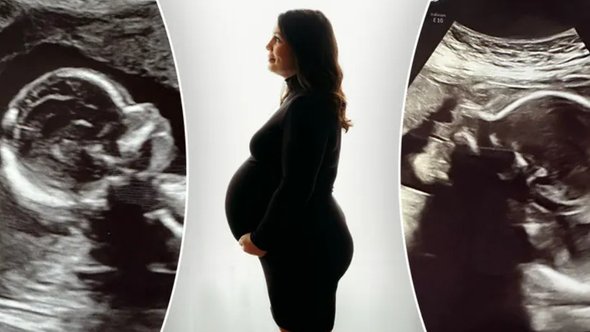

Американка с двумя матками родит двух девочек, которых вынашивает отдельно, но в одну беременность

Жительница американского штата Алабама с двумя матками в ближайшее время родит двух девочек, которые оказались зачаты и вынашиваются параллельно и отдельно каждая в своем органе. Об этом сообщает Fox News.

Американка Келси Хэтчер узнала, что у нее две матки, во время рутинного осмотра гинеколога в 17 лет. Сейчас ей 32 года и у нее уже есть трое детей, что называется, обычным путем, сейчас им шесть, четыре и два года. Когда Келси забеременела во второй раз она также хорошо себя чувствовала, но интуитивно почему-то волновалась и пошла к врачу.

Гинеколог осмотрела ее на восьмой неделе беременности, сказала, что все в порядке и заверила, что плод развивается нормально. Тогда Келси сообщила врачу, что на самом деле у нее есть вторая матка, и попросила повнимательнее сделать УЗИ еще раз. Обе женщины страшно удивились, когда оказалось, что в каждой матке у Келси развивается по одному полноценному плоду.

Сейчас женщина проживает последний триместр своей необычной беременности. Врачи предложили ей немного «переносить» ее, чтобы дождаться естественных схваток, так как из уменьшенного размера маток и развивающиеся в них дети тоже будут несколько меньше известных стандартов. Сама Келси хотела бы родить естественным путем. Но врачи пока не могут выбрать ни одну из тактик, безопасную для матери и новорожденных. У них есть сразу несколько сценариев на этот счет. Например, схватки могут начаться в одной матке, и тогда одна девочка родится естественным путем, а вторые роды будут стимулировать. Также, возможно, придется просто сделать кесарево, чтобы обе девочки родились одновременно.

фото, коллаж: личный архив семьи Келси Хэтчер